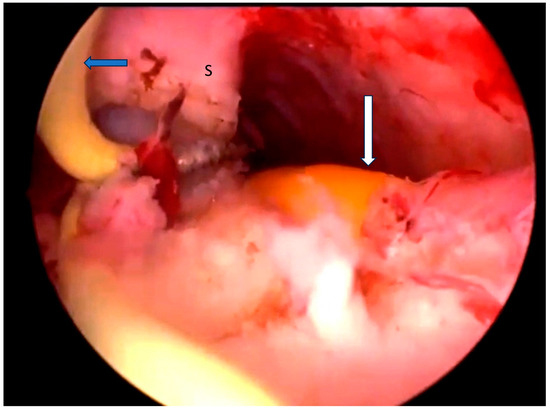

A pelvic examination revealed a longitudinal non-obstructing vaginal septum and distinct cervices on both sides. A transvaginal 3D ultrasound showed a complete uterine septum and a duplicated cervix. The ovaries and kidneys were normal. The pre- and postoperative pelvic MRIs are depicted in Figure 3. Like in the first case, hysteroscopic removal of the uterine septum up to the isthmic level, sparing the two cervices, and resection of the longitudinal vaginal septum were performed. A single uterine cavity was obtained (Figure 2b). The patient was discharged on the same day with a two-month estrogen pill regimen to prevent the occurrence of uterine synechia.

Figure 3. Preoperative and postoperative examination of case 2. (a) The preoperative MRI T2, WI, confirmed the presence of a Müllerian anomaly and identified it as a complete septate uterus, duplicated cervix, and longitudinal vaginal septum (Class U2bC2V1 of the ESHRE/ESGE classification). A complete septum with a thickness of 3 mm and a length of approximately 6 cm (measured from the intercolonial line) and 7.5 cm (measured from the level of the external contour of the uterus) was identified. (b) The postoperative MRI at 2 months confirmed the partial persistence of the septum in the supracervical region with the persistence of a slight indentation at the fundal level appearance of an arched uterus. (c) Three-dimensional ultrasonography performed 5 months postoperatively in which a normal uterine cavity was observed.

The postoperative MRI at 2 months is depicted in Figure 2b.

The control ultrasound examination performed 5 months after surgery revealed a relatively normal single uterine cavity, and the patient was scheduled to return in another two months for hysterosalpingography (Figure 2c).

However, hysterosalpingography was not performed because the patient became pregnant spontaneously. The pregnancy proceeded without complications until 25 weeks; the patient was subsequently lost to follow-up due to a change in their country of residence.